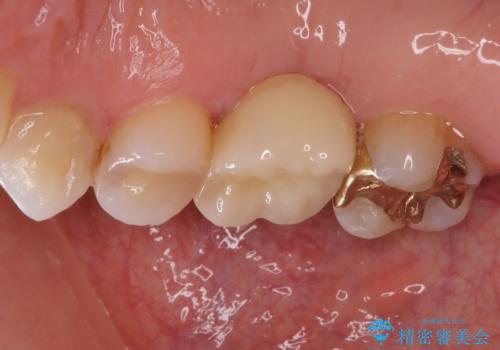

- 近医で奥歯の抜歯が必要であると指摘され、インプラント治療を希望して来院された患者様です。

診察の結果、大きな虫歯となっている歯は抜歯が望ましく、抜歯後にストローマンSLActiveを埋入することとしました。

さらに後方の歯は虫歯治療が途中であったため、ゴールドインレーにて修復治療行うこととしました。